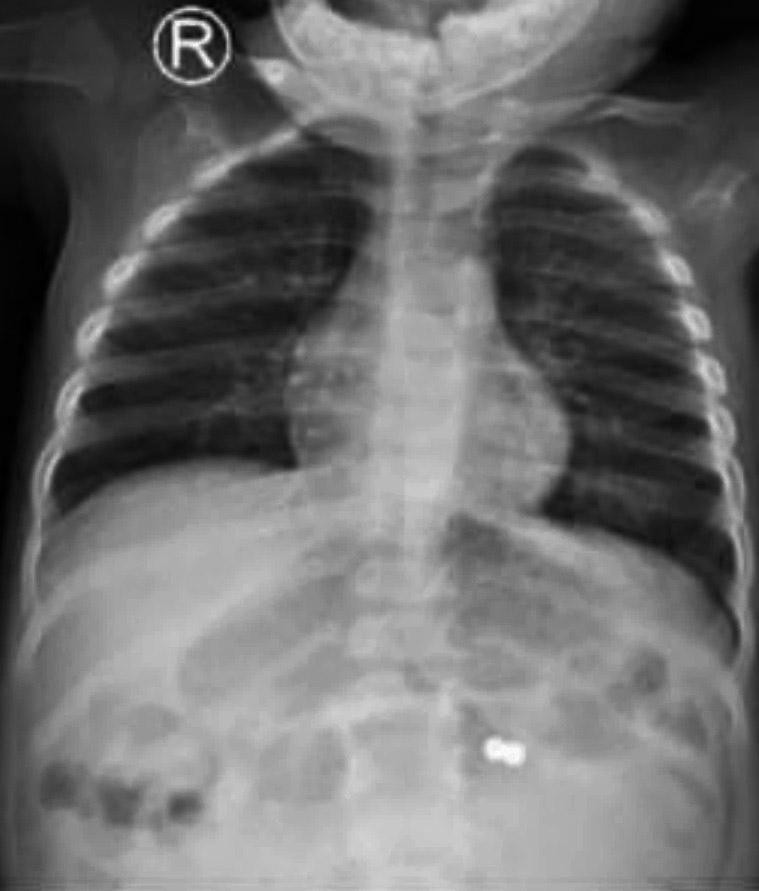

Sau thăm khám, bác sĩ tiến hành chụp X-quang vùng bụng thì phát hiện 2 dị vật cản quan có hình tròn. Tại khoa Ngoại Tổng hợp, bệnh nhi được chỉ định phẫu thuật lấy dị vật.

Trong quá trình thực hiện cuộc mổ, ê kíp phát hiện 2 viên nam châm hít vào nhau đã gây ra 5 lỗ thủng ở ruột non của bệnh nhi. Sau khi lấy dị vật ra khỏi cơ thể bệnh nhi, bác sĩ đã khâu các lỗ thủng ở ruột non. Hiện sức khỏe bệnh nhi đang dần bình phục.